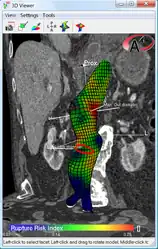

An aneurysm ruptures if the mechanical stress (tension per area) exceeds the local wall strength; consequently, peak wall stress (PWS)[29] and peak wall rupture risk (PWRR)[30] have been found to be more reliable parameters than diameter to assess AAA rupture risk. Medical software allows computing these rupture risk indices from standard clinical CT data and provides a patient-specific AAA rupture risk diagnosis.[31] This type of biomechanical approach has been shown to accurately predict the location of AAA rupture.[32]

Biomechanical AAA rupture risk prediction -